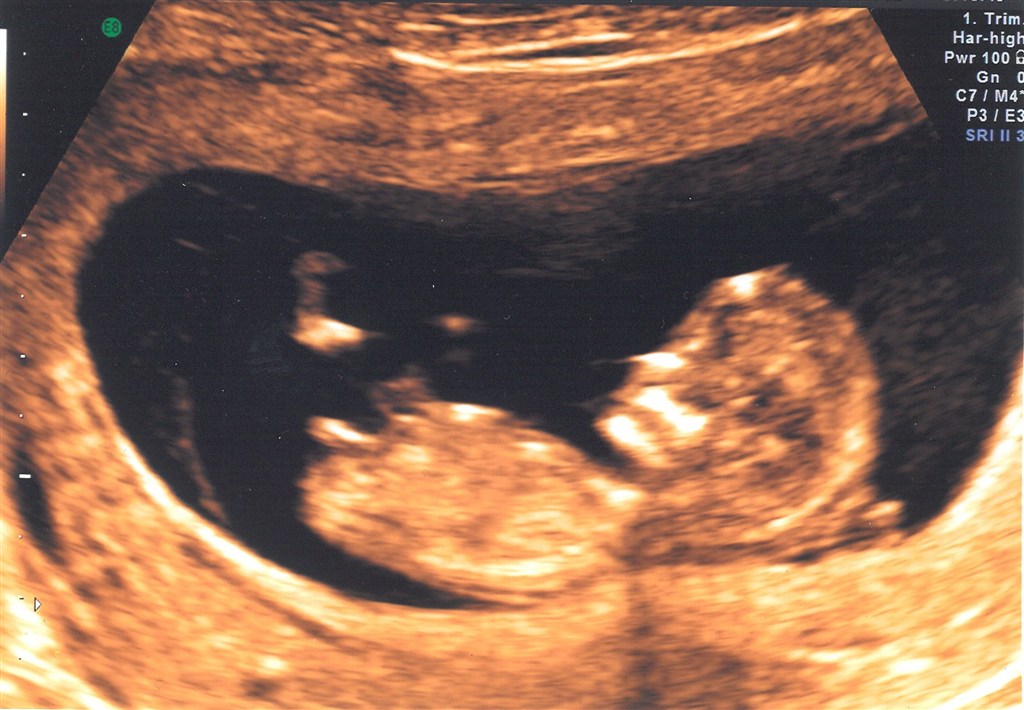

Er lige kommet hjem fra NF-skanning og det var bare den SØDESTE lille baby ♥ Ååååh det er bare såååå FANTASTISK at se den lille til skanning. Og så er det vidst en lille fodboldspiller der er derinde sådan som den kunne sparke igennem

Termin 10. sep. 2012 så er 11+4 idag.

I ska da ikke snydes for et billede

Vedhæftede fotos (klik for at se i fuld størrelse)

Hihi TAK - ja spændende om det ER en fodboldspiller. Det var i hvertfald sjovt at se som det bare var benene der kørte derud af